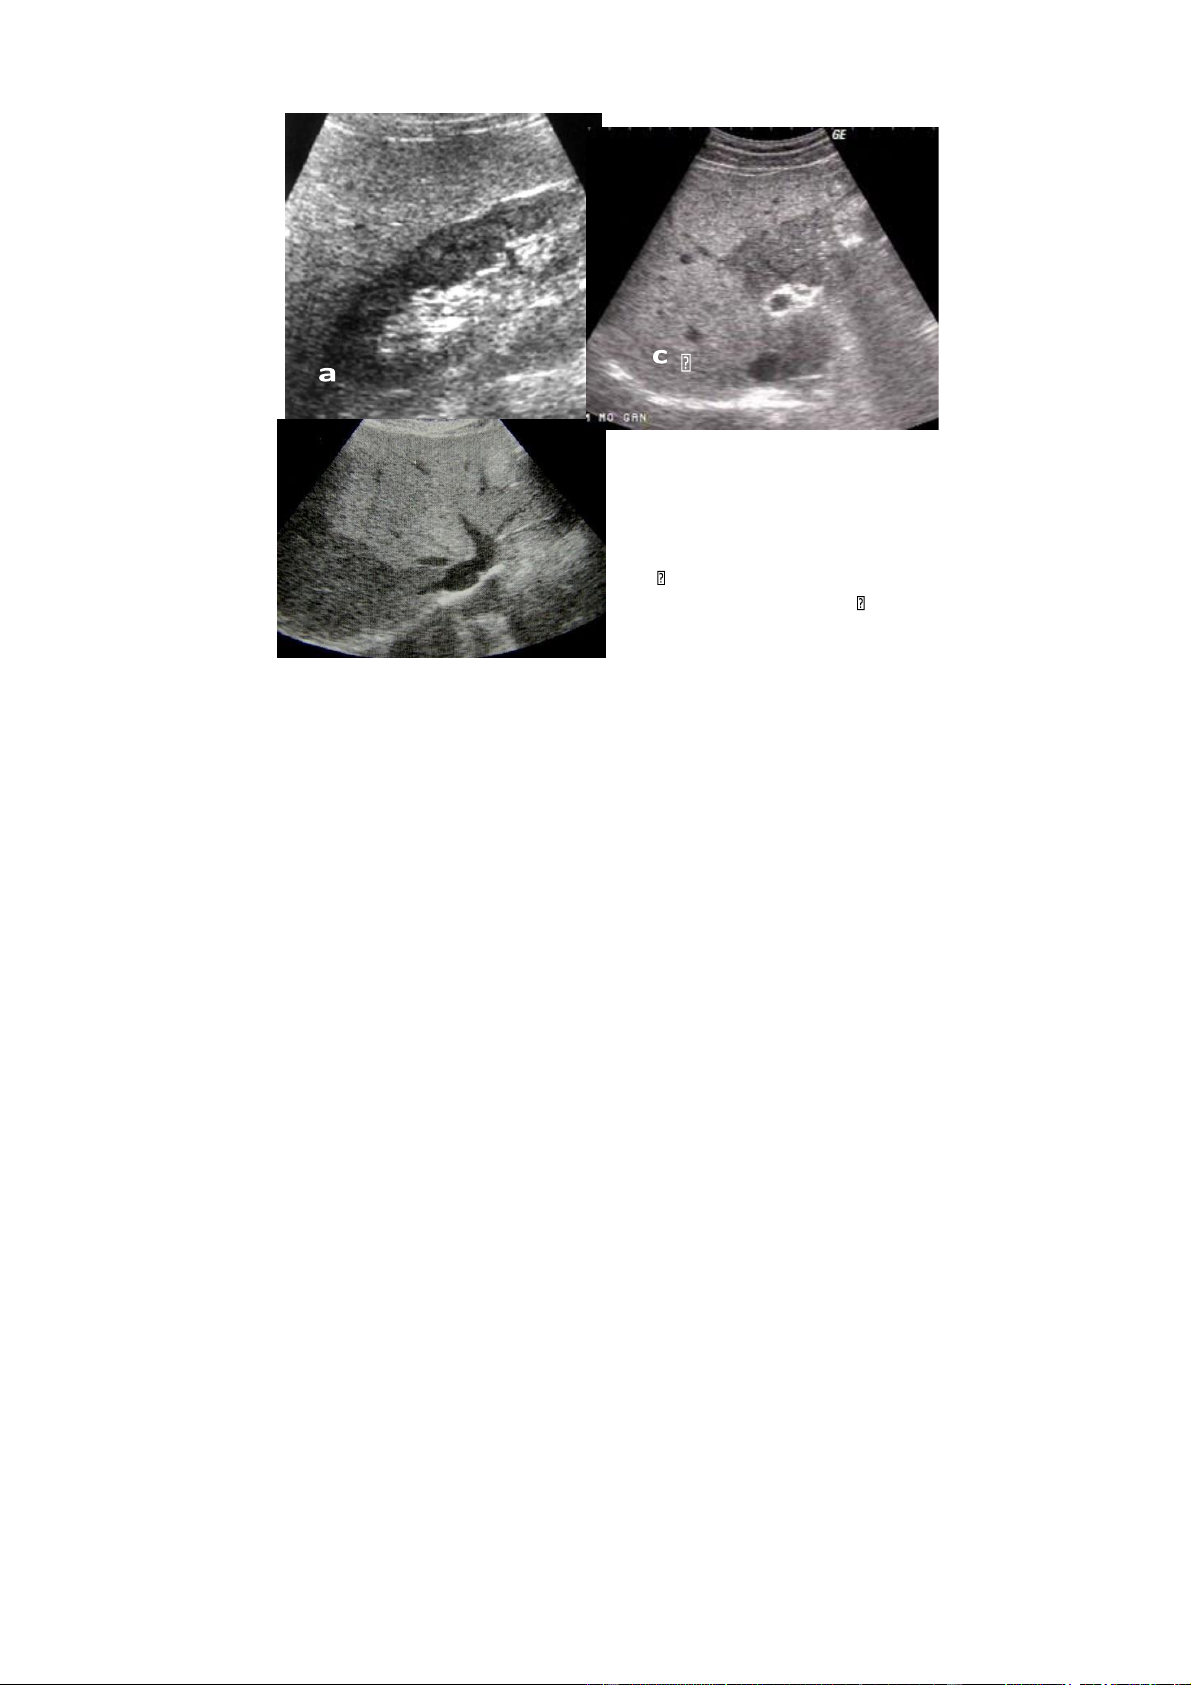

Chẩn đoán siêu âm

Thể điển hình

Chẩn đoán siêu âm u máu gan thường dễ đối với các khối u có kích thước

nhỏ (dưới 3cm đường kính). Khoảng 70-80% các trường hợp u máu có dấu hiệu siêu

âm điển hình biều hiện bằng một khối tăng âm đồng nhất hoặc lấm chấm, giới hạn

rõ với đường bờ tròn hoặc có nhiều vòng cung, thường nằm ở vùng dưới bao hoặc

tiếp giáp với một tĩnh mạch gan, không bao giờ có viền giảm âm bao quanh khối u

và đôi khi kèm theo dấu hiệu tăng âm phía sau. Tuy nhiên, Tăng âm phía sau khối

u không phải là dấu hiệu đặc trưng của u máu gan. Nhu mô gan xung quanh khối lOMoAR cPSD| 58490434 bình thường.

Hình. a và b. U máu điển hình

Hình. U máu không điển hình

a. U máu ít âm trên gan nhiễm mỡ

b. U máu không điển hình với những vùng giảm âm ở trung tâm

c. U máu lan toả giống như bản đồ d. U máu thể hang

Thể không điển hình

Thể không điển hình bao gồm các thể giảm âm, đồng âm và âm không đều.

U máu gan có thể giảm âm so với nhu mô gan xung quanh trong trường hợp gan

nhiễm mỡ nhiều. Cấu trúc âm không đều thường thấy ở những u gan có kích thước

lớn. Nó biểu hiện bằng một tổn thương có vùng ngoại vi tăng âm dạng u máu điển

hình và vùng trung tâm giảm hoặc rỗng âm. Cấu trúc này tương ứng với các tổn

thương xơ hoá, huyết khối, hoặc chảy máu trong khối u, đôi khi có thể có vôi hoá

trong khối. U máu thể đồng âm thường rất hiếm và dễ bỏ sót trên siêu âm. U máu lOMoAR cPSD| 58490434

thể hang thường hiếm gặp hơn, biểu hiện bằng vùng tổn thương có vỏ với nhiều hồ

dịch nhỏ, thành dày tăng âm. Một số trường hợp u máu lan toả chiếm cả một thuỳ

gan hay như hình bản đồ, đôi khi khối u có hai phần một phần nằm trong gan và một

phần nhô lên khỏi bờ gan.